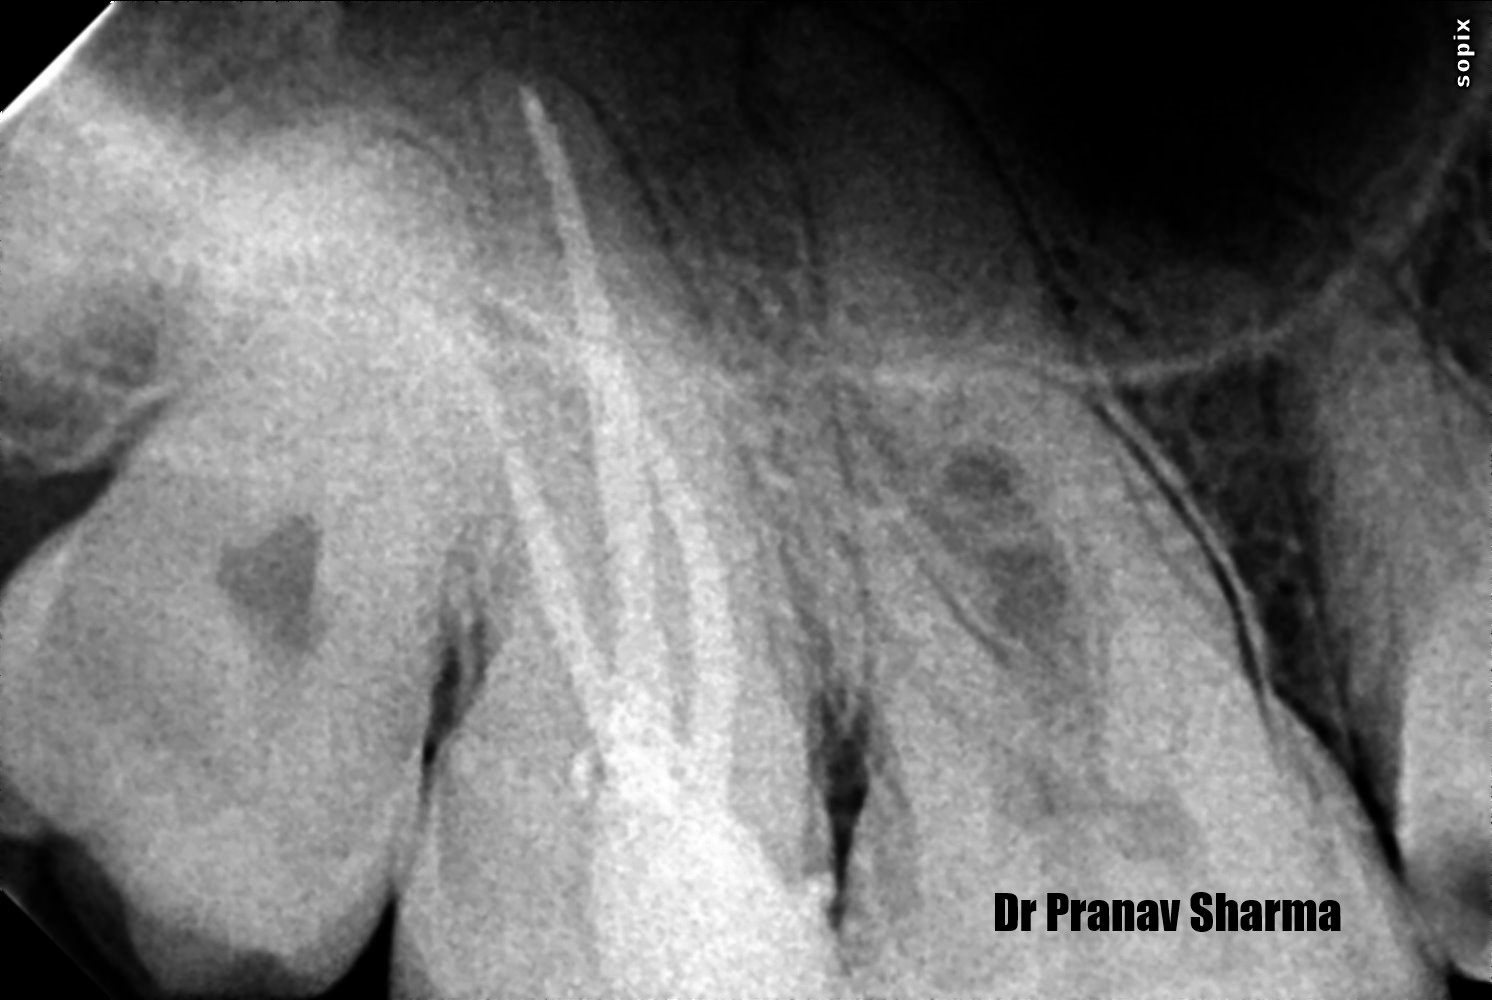

Xray